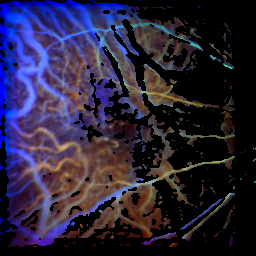

RGB images normalized to untreated patients with AMD

On this page, the colors in the images are normalized to the respective influx behaviour of untreated patients with AMD, so the colors visualize the influx relative to these patients (warm colors for rapid influx, cool colors for slower influx).

Control-proband

time of the maximum: 26.5 f ± 19.6%

visual acuity: 1.00